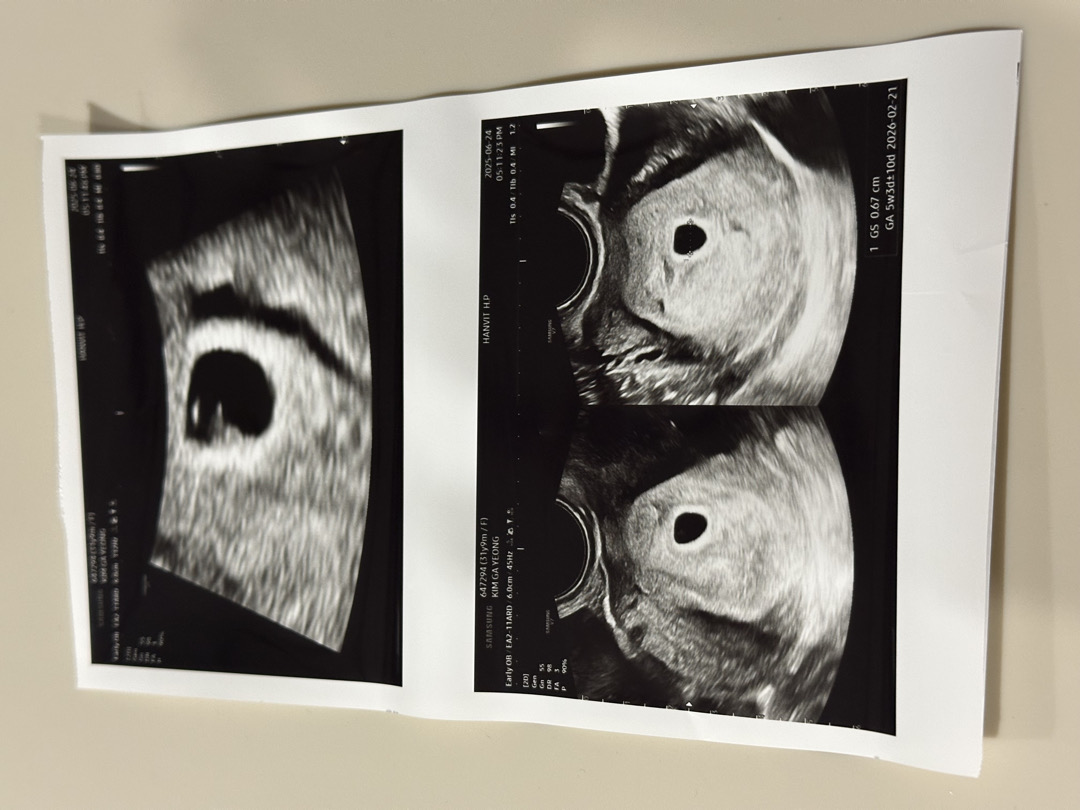

5주2일

애기집이랑 난황 확인했어요! 너무 애기가 작아서 자세히는 안보이지만 좋다고 2주 뒤에 다시 오라고 하시네요!^^